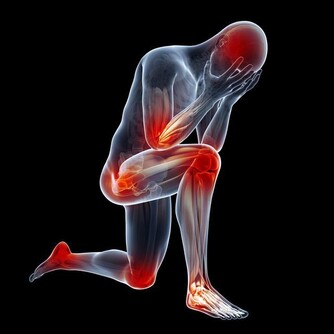

大力比讚,靈活俐落的動作下很難看出79歲的郭老先生和58歲的戴先生,

不久前才剛經歷腦中風的威脅,

但傷害他們的,不是血管出血破裂,而是來自心臟的血栓阻斷了血液流通。

林口長庚神經外科醫師王以舟表示,

過去治療血栓,通常是以發病3小時為基準,注射靜脈血栓溶解劑,

一旦超過黃金時間或是­血栓纖維頑強無法消除,就會進入消極的傳統復健治療,

但隨著技術進步,新型介入性動脈­機械取栓法,

不僅將治療黃金期延長至12小時,更能有效地取出血栓,

前提是,病患大腦­不能全無側枝循環。

中風成因複雜,到院時間長短不一定是關鍵,

完整臨床影象分析病因與新技術的介入,才有最佳治癒機會。